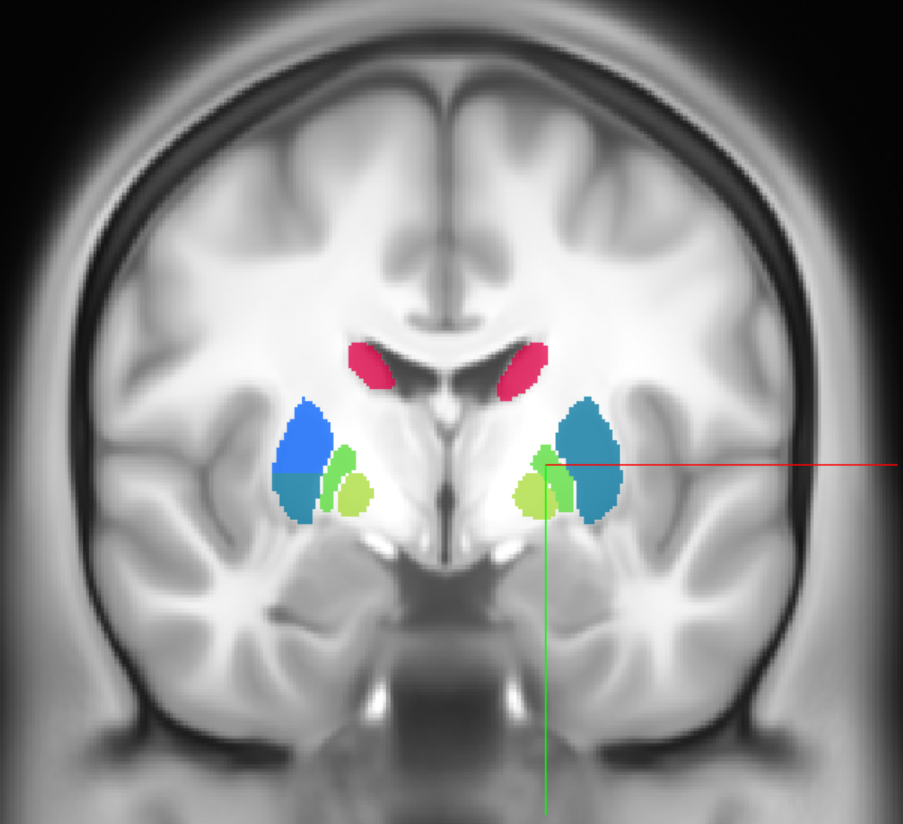

query_coordinate_neuroglancer = [-11, 3, -263]

acronym, name = annotation_image.get_atlas_label(query_coordinate_neuroglancer, physical_coordinate = True, neuroglancer_coordinate=True)

print(f"Coordinate {query_coordinate_neuroglancer} is in {acronym}: {name}")

Coordinate [-11, 3, -263] is in NACc: core of nucleus accumbens